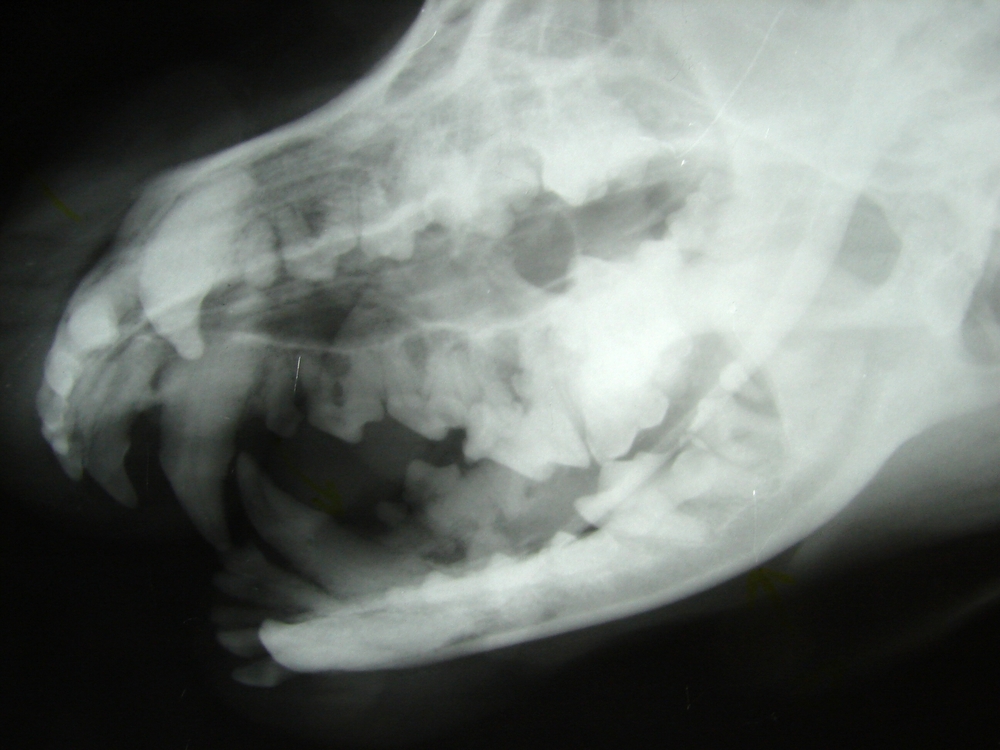

Cone Beam Computed Tomography (CBCT)

Cone Beam Computed Tomography (CBCT) is increasingly used in veterinary dentistry for its ability to produce high-resolution, 3D images of the teeth, jaws, and surrounding structures.